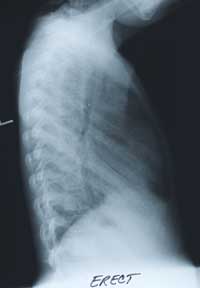

"Ongoing oxygen requirements after a pneumonia."

A six and half year old female presented with a five day history of

pleuritic chest pain, fever, and cough in April 1998. She had no hemoptysis.

The initial physical examination in April 1998 revealed, a child in mild respiratory distress, with cyanosis in room air. She was tachycardic, tachypneic and febrile. She was a thin girl (~5% for height and weight), with dry skin.

The respiratory examination revealed dullness to percussion in the right upper lobe, crackles and wheeze bilaterally. There was no clubbing and the rest of her examination was normal.

BELOW

is her CHEST X-RAY taken during the hospitalization.

Previous films from her NICU stay are not available.

Enlarge the CHEST X-RAY LEFT, enlarge the chest x-ray RIGHT.

WHAT ARE YOUR FINDINGS?